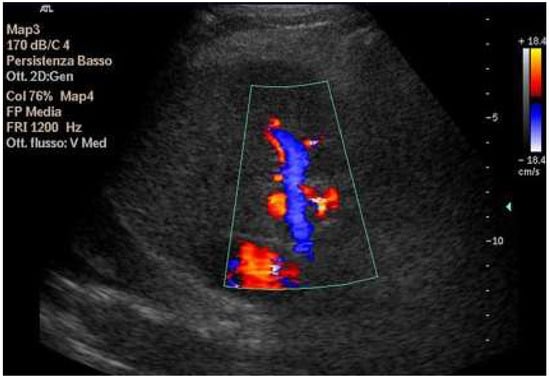

Doppler patterns in Fontan patients resemble those observed in chronic liver disease, including reduced portal flow velocity (mean flow velocity < 14 cm/s) [56]. The Fontan procedure inevitably alters hepatic venous waveforms on Doppler US (Figure 10, Figure 11, Figure 12 and Figure 13). Inverted portal flow has a specificity of 100% for diagnosing PHTN [57] (Figure 12). The hepatopetal phase pattern in the hepatic vein differs between patients with total cavo-pulmonary anastomosis (including both lateral tunnels and extracardiac conduits) and those with atrio–pulmonary connection [58,59,60]. In atrio–pulmonary connection, hepatopetal flow is preserved (Figure 10), reflecting the exclusion of atrial contribution to venous circulation, whereas in total cavo-pulmonary anastomosis, flow reversal (Figure 11) occurs only during early expiration. Similarly to congestive heart failure, hepatic veins and the IVC are dilated, with abnormally increased hepatic vein pulsatility, regardless of the anastomosis technique [54,61,62]. The loss of the normal three-phase Doppler pattern in hepatic veins is universal following bi-cavo-pulmonary surgery due to the absence of atrial contraction. The presence of a monophasic pattern indicates advanced liver injury [63].

Figure 10.

Doppler Ultrasound of the middle hepatic vein showing the loss of the normal three-phase pattern due to the absence of atrial contraction.

Figure 11.

Preserved hepatopetal portal flow in atrio–pulmonary connection.

Figure 12.

Inverted portal flow in cavo-pulmonary anastomosis.

Figure 13.

Changes in hepatic vascularization in a patient with FALD. The middle hepatic vein is patent, although irregular, within the context of the parenchymal nodularity.